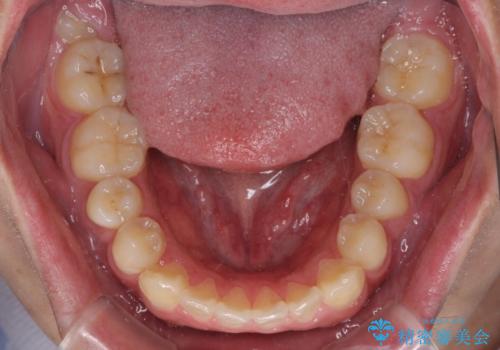

- 八重歯と前歯の隙間を気にして来院された患者様です。

八重歯の改善のため、奥歯を後方に移動させていくこととし、患者様と相談の上、ワイヤー装置にて矯正治療を行うこととしました。

治療装置については、自己管理が煩わしいとのことで、マウスピースではなく目立ちにくいワイヤー装置を選択されました。